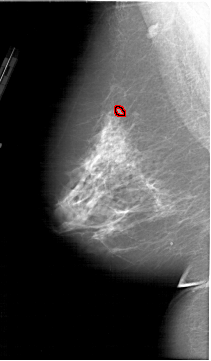

A_1913_1.LEFT_MLO

LEFT_MLO LINES 6481 PIXELS_PER_LINE 3796 BITS_PER_PIXEL 12 RESOLUTION 43.5 OVERLAY

FILE: A_1913_1.LEFT_MLO.OVERLAY

TOTAL_ABNORMALITIES 1

ABNORMALITY 1

LESION_TYPE CALCIFICATION TYPE PLEOMORPHIC DISTRIBUTION CLUSTERED

ASSESSMENT 4

SUBTLETY 4

PATHOLOGY BENIGN

TOTAL_OUTLINES 1